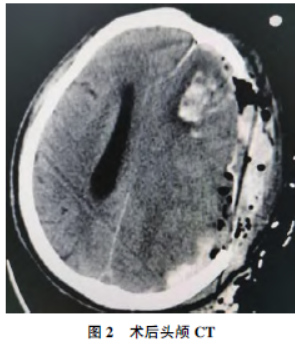

该患者在ICU累计治疗3d,术后当日复查头颅CT提示:脑疝形成,较前进展,蛛网膜下腔出血,左侧额叶、胼胝体膝部脑出血、双侧基底节区脑梗死

,较前新出(图2)。